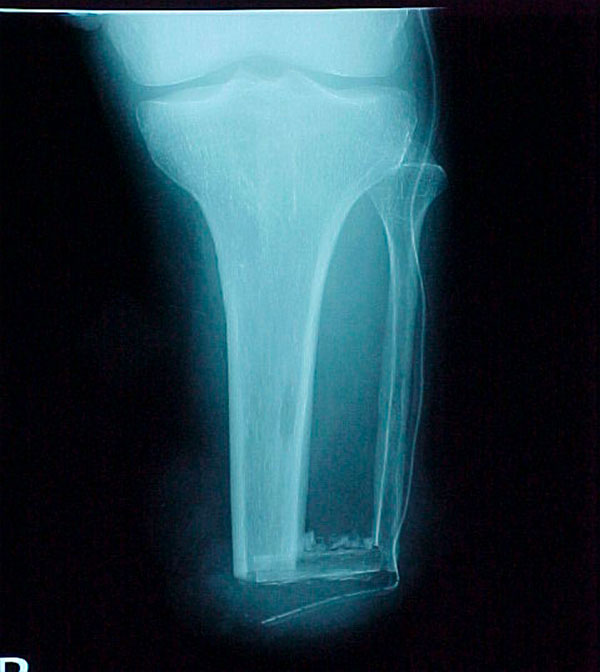

- Primary Objective Observational study comparing outcomes following limb salvage versus amputation of a severe distal tibia, ankle, and/or foot trauma